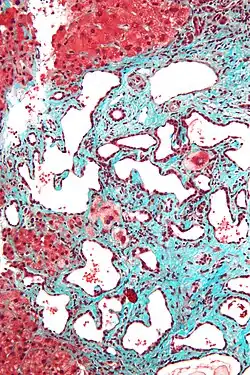

Micrograph of a bile duct hamartoma. Trichrome stain. Intermediate magnification -

Low magnification micrograph of a bile duct hamartoma. Trichrome stain. -